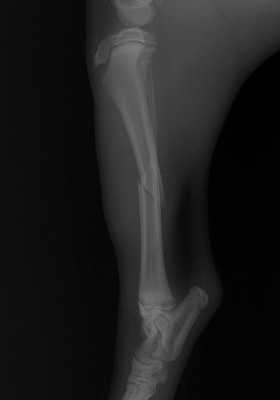

家の中で遊んでいると「キャイーン」という悲鳴と共に片方の足を地面に付く事が出来なくなり来院されました。レントゲンを撮り調べてみると骨折していることが判明。